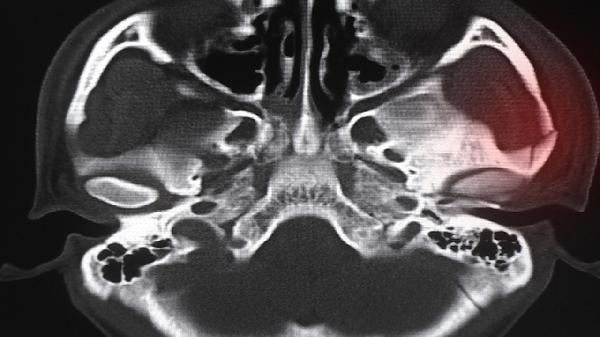

在醫(yī)生指導(dǎo)下通過手法按摩幫助軟骨復(fù)位。用拇指指腹沿鼻小柱兩側(cè)由下向上輕柔推壓,每次持續(xù)5分鐘,需避免用力過度導(dǎo)致二次損傷。該方法對嬰幼兒先天性軟骨畸形或輕度外傷性移位可能有效,成人需結(jié)合影像檢查評估。

嚴(yán)重軟骨畸形需行鼻小柱重建術(shù)或軟骨復(fù)位固定術(shù)。通過鼻腔內(nèi)切口調(diào)整軟骨位置并用可吸收線固定,術(shù)后需佩戴鼻夾板1個月。手術(shù)適用于先天性畸形、外傷后錯位愈合或假體移位導(dǎo)致的功能障礙者。